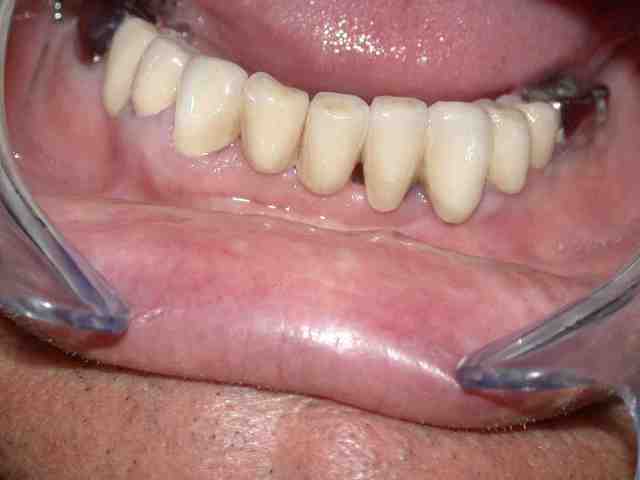

suite et fin

réalisation du haut et pose

bridge dentoporté secteur droit(jr mettrai pas les numéros na !) dents unitaires sur les implants

et tant pis pour le métal au fond...